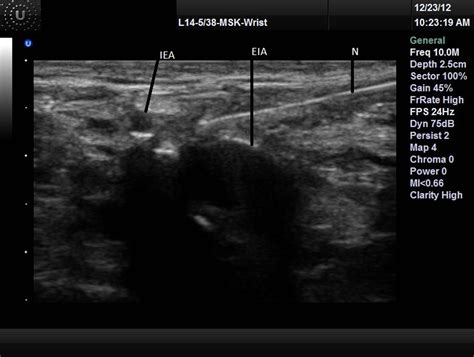

2. Place the ultrasound probe transversely over the inguinal crease to visualize the femoral nerve, artery, and vein.

3. Identify the femoral nerve, which appears as a hyperechoic structure lateral to the femoral artery.

4. Insert the needle in-plane with the ultrasound probe, aiming for the femoral nerve.

5. Aspirate to ensure the needle is not in a blood vessel, then inject the local anesthetic while visualizing the spread of the anesthetic around the nerve.